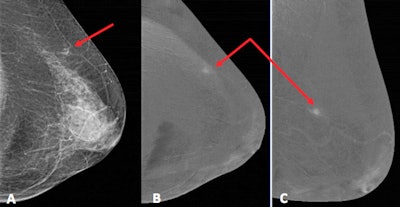

Malignant lesions tend to show intense enhancement -- due to their hypervascularization -- and also tend to present spiculated margins. CESM helps to detect other associated lesions in the same or contralateral breast.

Benign lesions are highly prevalent and in many cases, they share radiological similarities with malignant processes, and it is important for the radiologist to know how to distinguish them and to correlate the radiological appearance with a patient's risk factors, the researchers continued.

Many malignant entities present enhancement in CESM as they are hypervascular, but there are benign diseases that can also enhance and therefore present as false positives. A tool that can reduce false positives is the kinetic assessment of contrast uptake curves, which in CESM are not entirely comparable with those of MRI, they wrote.